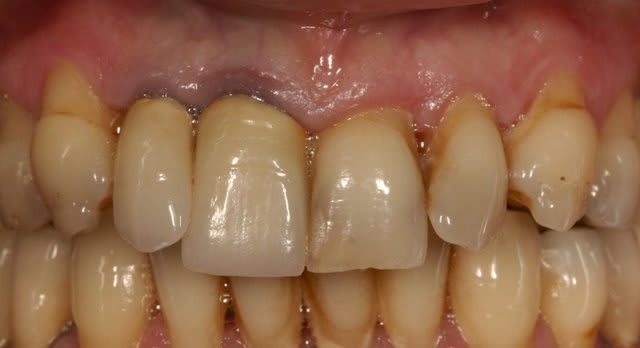

Je souhaiterais savoir comment vous gérer ces cas de mylolyses/érosions importantes sur les antérieures.

Pour le cas iconographié, je pensais à des facettes (histoire de donner une seconde jeunesse au sourire), mais je me demande comment réaliser mes préparations, s'il faut combler au compo pour éviter de surtailler autour, etc.

Avant d'envisager la moindre facette, il va falloir je pense revoir l'occlusion de ta patiente: courbe de Spee foirée à gauche, parafonction 21,22, vestibulo-version 12 suite DDM inf.

Gros point positif ici: la patiente semble avoir une hygiène impeccable et dégage assez peu les collets au sourire, d'où une certaine facilité à gérer l'esthétique "rose".

Après pour la partie technique pure au niveau antérieur, tout dépend de l'état d'usure palatine, et de lq stabilisation du bruxisme/parafonction, (comme demandé plus haut par GP) une photo occlusale peut nous guider pour connaître la meilleur thérapeutique à adopter, et l'éventail est large: du simple composite à la couronne périphérique en passant par la facette bilaminaire (au fait Gp se serait sympa de partager ce genre de cas avec les Nonoliens ;-)).

Ma question est purement technique. En palatin on ne note pas d'usure. Comment gérer la profondeur à rattraper, sur 23 par exemple, et comme tu l'indiques, Cingulum, quid de la qualité du collage sur ce type de dentine sclérosée? Avez-vous des trucs et/où astuces ?